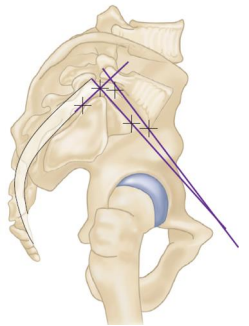

Espondilolisteses

• Qual a definição e as principais características da incidência pélvica (IP)?

A

• Ângulo entre a linha perpendicular ao platô superior do sacro e a linha entre o ponto médio do platô superior do sacro até o centro da cabeça do fêmur

• Normalidade: 50 a 55°

• Principais características:

• Aumentado nos pacientes com listese (escorregamento)

• Parâmetro fixo → anatomia individual

• NÃO prediz a progressão da deformidade

7

Q

• Qual a definição e as principais características do Tilt Pélvico (TP)?

Depende da posição da pelve

• Ângulo entre a linha que liga o centro da cabeça femoral ao centro do platô de S1 e a linha perpendicular ao solo, passando pelo centro da cabeça femoral

• Pode ser alterado pela translação e retroversão pélvica

Quanto > o Tilt Pélvico (TP) > a retroversão da pelve

Bizu: Tilt → Teto (a linha vai para o teto)

8

• Qual a definição do Slope Sacral (SS)?

• Ângulo entre a linha paralela ao platô superior de S1 e a linha paralela ao solo

• Relação direta com a incidência pélvica e tilt pélvico

• Deve ser 30°

Bizu: Slope Sacral → Solo

9

• Na avaliação radiográfica da pelve, com pode ser calculada a incidência pélvica (IP)?

• IP = TP + SS

• Tilt Pélvico (TP)

• Slope Sacral (SS)